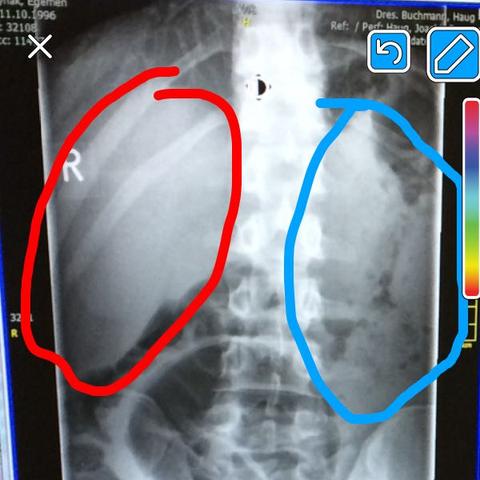

Was bedeutet schatten auf der lunge. Findet sich im Röntgenbild ein Schatten auf der Lun. Ein Tumor kann dementsprechend entzündlicher gutartiger benigne oder bösartiger maligne Natur sein. Was steckt hinter dem Schatten auf der Lunge auf dem Röntgenbild.

Da ist ein Schatten auf Ihrer Lunge wer diese Diagnose hört dürfte erschrecken und befürchten dass er Lungenkrebs hat. Möglich sind auch andere Ursachen wie etwa Lungenentzündung oder Tuberkulose. Zeigt das Röntgenbild einen Fleck auf der Lunge medizinisch Lungenrundherd genannt kommen verschiedene Ursachen infrage.

Millionen Atemwegserkrankungen Schatten Auf Deutschen Lungen Gesellschaft Sz De